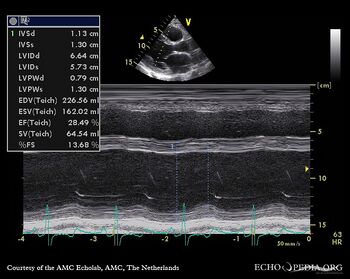

Case 12

| Courtesy of: J. Vleugels, AMC, The Netherlands | |

| spontaan echocontrast 12 | spontaan echocontrast 1 |

| spontaan echocontrast 3 | spontaan echocontrast 4 |

| spontaan echocontrast 5 | spontaan echocontrast 6 |

| spontaan echocontrast 8 | spontaan echocontrast 25 |